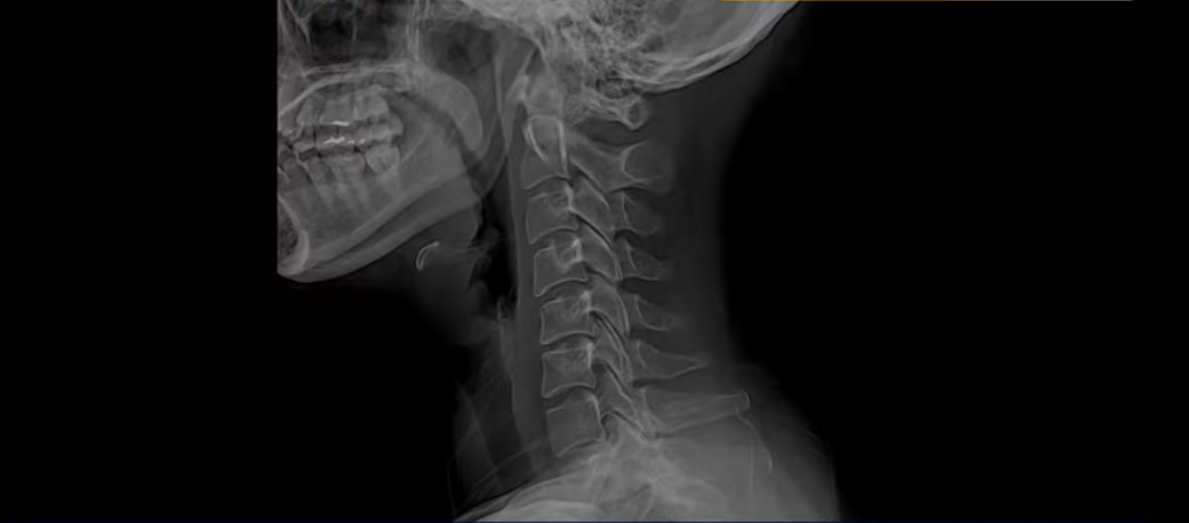

이 환자분 X-ray, MRI 보고 간단히 설명 드린 후 왜 목디스크 치료가 허리디스크에 비해 훨씬 더 쉬운지 자세히 설명 드리겠습니다.

이분 X-ray에서 보시다시피 완전한 일자목과 거북목입니다.

이런 목 형태를 가지면 항상 목이 뻐근하고 담이 걸린 것처럼 아프기 쉽습니다. 그리고 이런 거북목의 형태는 목에 엄청난 부담을 주기 때문에 디스크가 퇴행되면서 언젠가는 찢어지기 쉽습니다. 그래서 결국 5번 6번 목디스크가 찢어지면서 오른쪽으로 밀려나옵니다.

이 환자분도 아까 X-ray에서 보여드렸듯이 아주 심한 일자목, 거북목이 있고 그 결과로 목의 거의 모든 마디가 다 퇴행이 진행되어 있죠. 즉 거북목은 모든 목질환, 특히 목디스크, 목협착증의 어머니 질환이며 그래서 목디스크를 치료하기 위해서는 반드시 거북목 때문에 짧아지고 뭉치고 굳고 뒤틀린 목 주변 근육들을 잘 치료해줘야 합니다.